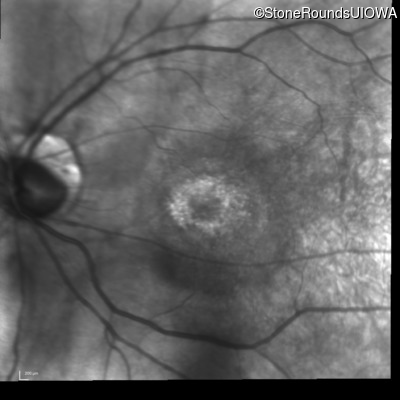

Infrared Fundus Photograph - Right - 20/32 +1

Exemplar

Infrared Fundus Photograph - Left - 20/32 -1